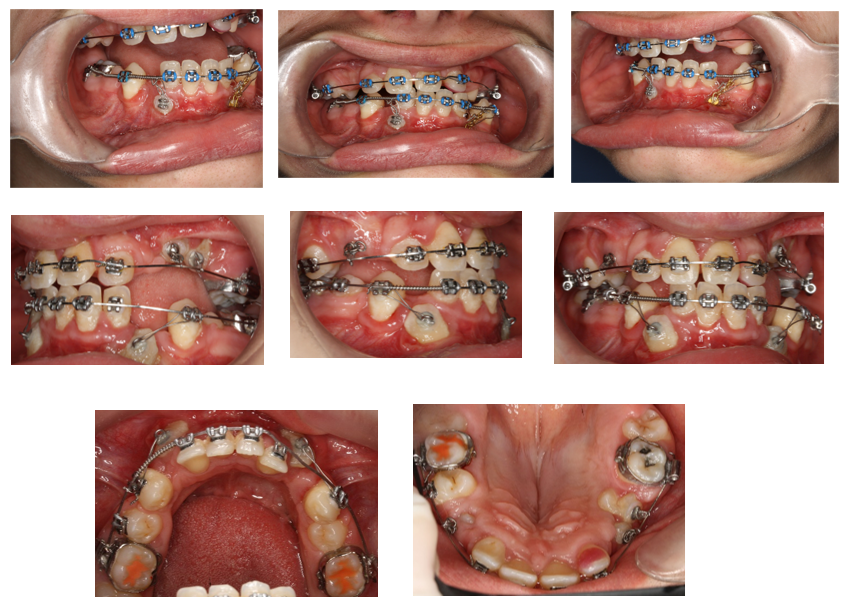

In January 2022 a surgical exposure in local anesthesia of 33 and 43 was provided, and the attachment was bonded immediately. The canines were loaded only with light distal forces to avoid interference of these teeth crowns with the roots of the lower incisors. (Fig. 16)

Figure 16: Top 3 pictures: Intraoral photographs after surgical exposure of the lower canines in January 2022. The brackets were bonded immediately, the same as the loaded forces. The bottom pictures were taken in January 2024, after surgical exposure of teeth in the upper right and left quadrant in March 2023.